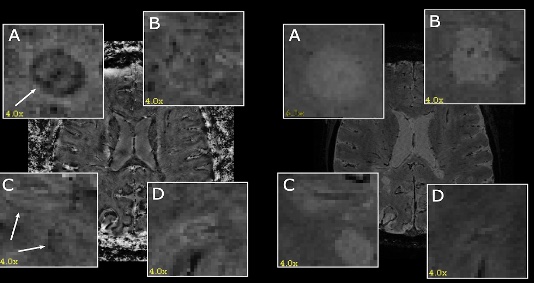

9. Explainable AI for the Detection of Rim Lesions in 3D MRI Scans

This project aims to contribute to the development of artificial intelligence-aided (AI-aided) tools for the prognosis of multiple sclerosis (MS) disease in clinical practice. The focus of this project is on the detection of rim lesions in MS, which are specific patterns of brain lesions visible on magnetic resonance imaging (MRI) scans [1]. Rim lesions are believed to indicate ongoing inflammation and active demyelination, particularly in the outer edges of pre-existing lesions.

The current manual process of detecting rim lesions in MRI scans is time-consuming and requires significant expertise. Therefore, automating this task through deep learning (DL) techniques, specifically 3D semantic segmentation, appears to be a promising solution [2]. However, due to the inherent noise in ground truth segmentation masks for both lesion detection and delineation, employing weakly supervised segmentation (WSS) methods becomes an attractive alternative. In this project, we will explore the use of saliency detection methods for weakly supervised segmentation purposes [3]. Thus, the student project will encompass two main stages: 1. Creating a DL model for a preliminary regression task of the number of lesions in a scan. 2. Applying Explainable AI (XAI) techniques, particularly saliency maps [4], for the detection of rim lesions.